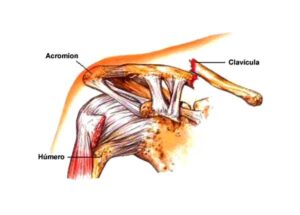

Las fracturas óseas pueden variar en gravedad, desde una simple fisura hasta una rotura completa en varias partes. El tipo de fractura influye en las opciones de tratamiento. Las fracturas capilares o por estrés son pequeñas fisuras difíciles de detectar, mientras que las fracturas completas rompen el hueso en dos partes. Las fracturas abiertas implican que el hueso atraviesa la piel, y las fracturas conminutas significan que el hueso se ha fragmentado en múltiples piezas.

El objetivo del tratamiento de las fracturas es permitir que el hueso sane y se fusione de nuevo. A menudo, esto puede lograrse inmovilizando el hueso durante varios meses con la ayuda de una escayola y una férula. Cuanto más grave es la fractura, más probable es que se recomiende la cirugía.

Por ejemplo, una fractura abierta o conminuta requerirá una intervención quirúrgica para garantizar que el hueso vuelva a crecer por completo y soporte su peso con seguridad. La reparación quirúrgica implica el uso de varillas, tornillos o placas metálicas para fijar el hueso en su sitio o alinearlo mientras se cura.